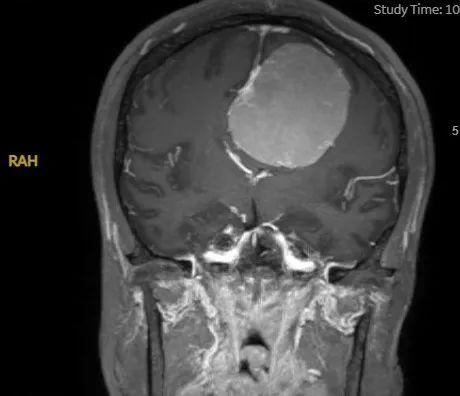

昆山市一医院神经外科成功切除颅内功能区巨大脑膜瘤

头痛半年,居然是脑袋里长了瘤

手术前

脑瘤体积大,手术难度高